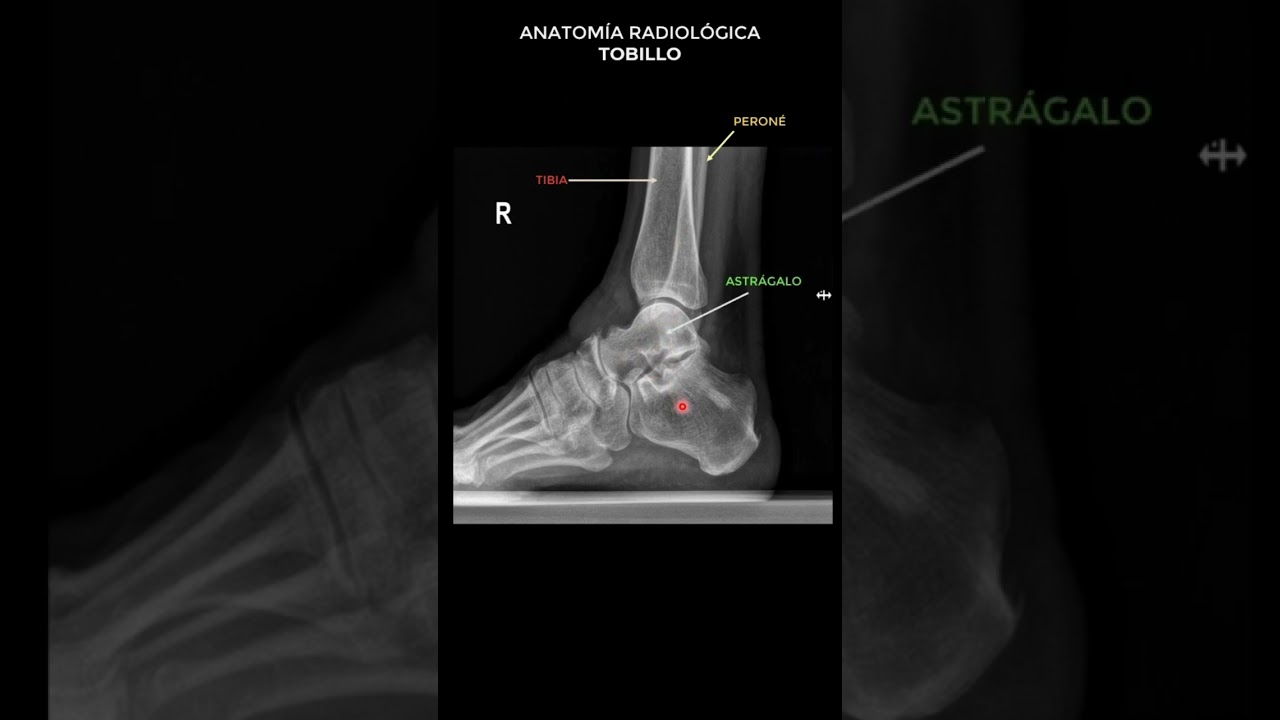

¿Un esguince se ve en una radiografía? Todo lo que necesitas saber

un esguince se ve en una radiografia

Cuando hablamos de lesiones deportivas o accidentes cotidianos, uno de los términos más comunes que escuchamos es «esguince». Esta condición, que afecta a los ligamentos, puede causar dolor e incomodidad significativos. Pero, ¿cómo se diagnostica …